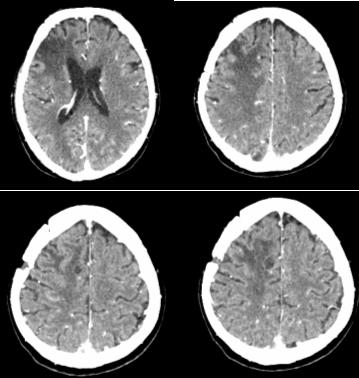

Third clinical case

A 57-year-old man with non-small cell lung cancer NSCLC/ adenocarcinoma is presented. Due to complaints of headache, nausea and vomiting after CT, two brain metastases were proven in the right brain hemisphere with frontal and parietal parasagital localization. The right frontal metastasis with dimensions 32mm/ 30mm was surgically removed. Postoperatively, intensitymodulated WBRT with DD 2.5 Gy up to TD 27.5 Gy with boost in the right parietal parasagital metastasis up to OOD 33 Gy with DOD 3 Gy / total radiobiologically equivalent dose (BED) 60 Gy was carried out (Figure 8). After 4 months, in another medical institution, despite the lack of cerebral symptoms, local RT by the VMAT method in the area of same metastasis up to TD 20 Gy with DD 4 Gy was performed. After 7 months of the second RT, of CT with venous contrast, a parasagittal cystic lesion up to 14 mm in size in the right parietal supratentorial area was visualized, most likely a necrotic brain tissue with pronounced frontoparietal edema (Figure 9).

Figure 9: CT of the brain - A parasagittal cystic lesion up to 14 mm in size in the right parietal supratentorial area with frontoparietal edema, most likely a necrotic brain tissue.

Whole-brain radiotherapy with boost RT

Although different fractionation schedules of WBRT do not influence survival [32], it appears that escalating the dose to the metastatic lesions increases intracerebral control as well as OS, compared to WBRT alone [53,54]. WBRT with 3D conformal boost is a feasible technique which improves the quality of life (QOL) of patients with a reduced number of brain metastases, regardless of the fractionation regimen or the total dose administered to the metastatic lesions [34]. In the third clinical case, with NSCLC after WBRT with VMAT boost in the brain metastasis to cumulative biological equivalent dose (BED) 60 Gy (Figure 8), a second hypofractionated Intensity modulated Re-irradiation with DD 4 Gy up to TD 20 Gy was conducted. Late side effects appear after 6 months of RT or later include visible radionecrosis of the brain with fields of focal coagulation necrosis and progressive microvascular occlusion with increased risk of stroke [55-58]. Data exist concerning the re-irradiation of brain tumors to a median cumulative BED (biological equivalent dose in 2Gy fractions) of 200Gy, with at least one year between the two treatments. Longterm complications related to the retreatment were seen in patients with a BED2>204Gy (α: β=2 Gy) [59]. Although the BED does not exceed 200 Gy, the radionecrosis of the clinical case is due to the short time (less than 6 months) between the retreatment as well as the high daily dose of 4 Gy (Figure 9).